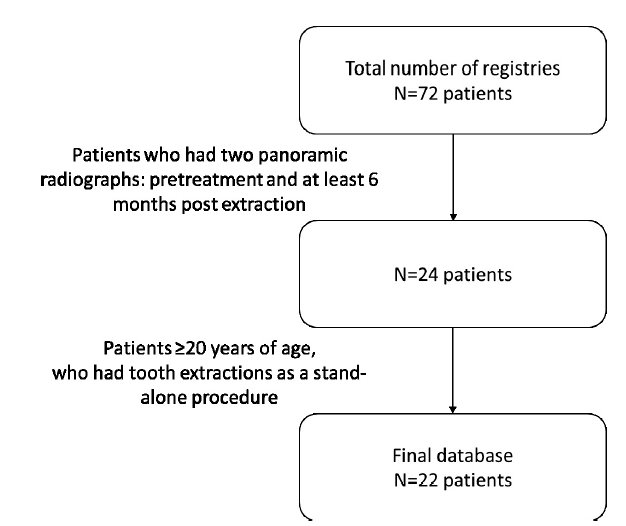

The research protocol was approved by the Ethical Committee of Rambam Health Care Campus, Haifa, Israel (approval # 0435-15-rmb). An initial database of 72 dental files of patients who underwent extraction of either the maxillary second premolar, first molar, or second molar at the Department of Periodontology between July 1996 and March 2016 were screened for potential inclusion in this retrospective study. Twenty-four patients from the initial database, who had both a pretreatment (Tb) and at least 6 months post-extraction (Tf) panoramic radiographs, were further screened for possible inclusion in the study. Finally, 22 patients $\geq $ 20 years of age, who had tooth extractions as stand-alone procedures (without concomitant flap elevation, socket preservation, guided bone regeneration, immediate implant placement or sinus perforation during tooth extraction), were included in the study (Fig.1).

Fig. 1.

Fig. 1.Database flow chart.